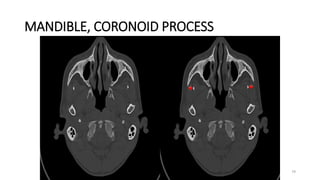

MANDIBLE, CORONOID PROCESS